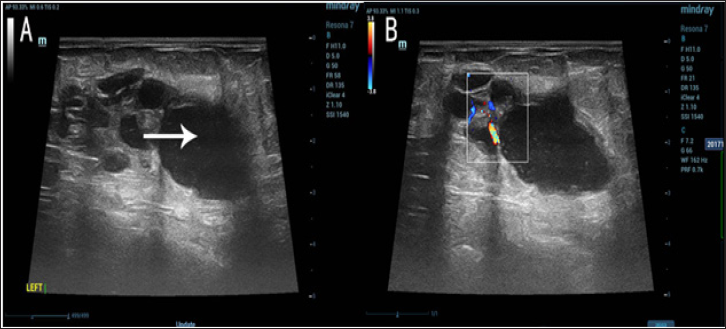

A 54-year-old postmenopausal woman presented with a cystic mass in the left breast for one week. Physical examination disclosed the breast lump was located in the lower outer quadrant, which was 5cmx 2cm, indolent, mobile, ill-defined, hard, with no nipple dischargeand retraction of nipples. Breast ultrasound showed a lobulated cystic-solid (mainly cystic) mass (Figure 1). Fine needle aspiration biopsy ofthe breast lump was done, and the smear showed a large number of tissue cells and a small amount of glandular epithelial cells with uniform size, which suggest consideration for cystic lesions. The patient and her family had no history of breast disease previously. Since the evidence from the fast pathological examination was not strong enough to diagnose this breast lump as malignant, the patient underwent local excision of the mass at first. Four days later, the result of the routine pathological examination was reported. Grossly, the cut surface revealed a 2.5cm x 2cm x 2cm tumor which showed multiple cystic as a honeycomb, and the cysts were filled withgelatinous secretions.Microscopically, the tumor showed a varied histological pattern with cysts, microcystic and solid structure, the tumor cells were in the same shape, the mitosis was rare, and eosinophilic secretions were found (Figure 2). Histo chemical staining showed the cystic contents were filled with PAS-positive dense eosinophilic material resembling thyroid colloid. However, the contents of the cyst were negative for thyroglobulin(TG) and thyroid transcription factor-1(TTF-1). The expression of S-100(Figure3A), GATA binding protein 3 (GATA3) and estrogen receptor(ER) was positive in tumor cells, while the expression of progesterone receptor(PR) and human epidermal growth factor receptor-2(HER-2) was negative (Figures 3B & 3C).The cells adjacent to tumor were negative in expression of P63 and calponin (Figures 3D-3F), which suggests myo epithelial deficiency that considered as invasive lesions. Taken together, the diagnosis is likely to be invasive CHC, thus breast-conserving surgery with sentinel lymph node biopsy was performed successively. The pathological examination post-surgery showed the sentinel lymph nodes were free of tumor metastasis. Then the patient underwent subsequent radiotherapy. The three-month follow-up of the postoperative period was uneventful.

Figure 1: Breast ultrasound showed a lobulated cystic-solid (mainly cystic) mass.